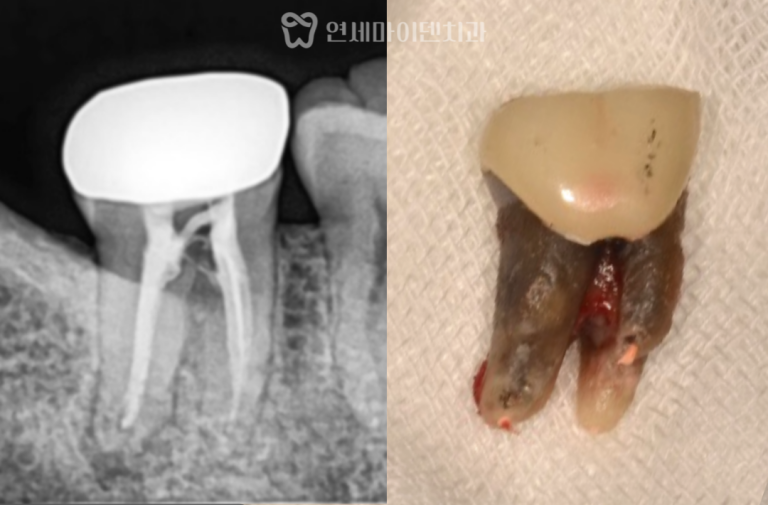

치료 전 방사선 사진을 보면

치아가 쓰러진 문제도 있었지만

무엇보다 뼈의 폭과 높이가

많이 줄어든 상태였습니다.

1차 수술: 발치, 염증 정리, 식립과 이식 동시 진행

첫 단계에서는

아래 1개, 위 2개

총 3개의 임플란트를 계획했습니다.

위쪽은 상악동이 내려와 있어

상악동 거상술과 뼈이식을 함께 시행한 뒤

그 공간에 임플란트를 식립했습니다.

아래쪽은 뼈 상태가 비교적 유지되어 있었지만

안정적인 고정을 위해

필요한 부위에 뼈이식을 병행했습니다.

즉, 발치가 필요한 부위는 발치를 하고

염증을 정리한 뒤

식립과 뼈이식을

하루에 함께 진행한 케이스였습니다.

발치 후 내부를 확인하니

오랜 기간 축적된 세균막이 관찰되었습니다.

이러한 세균막은

치주질환을 악화시키는 원인이 되기 때문에

초기 정리가 매우 중요합니다.